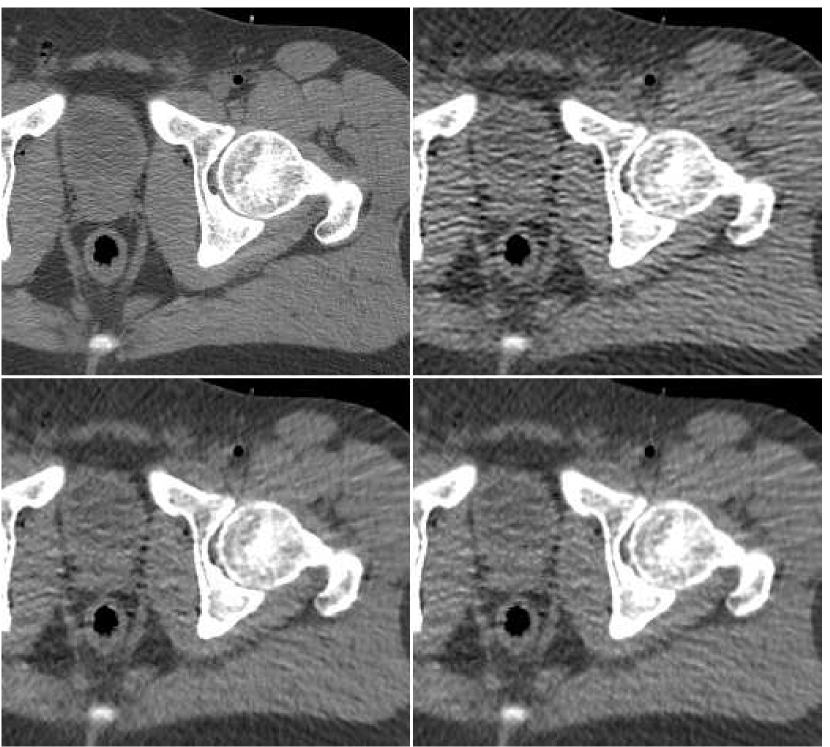

In Figure 6 we present a reconstruction of a test image. This test image is taken cm away from the region where the training data was taken from. The middle upper image is the result of a fusion of the number of FBP versions, performed with the trained ANN. By the visual impression, the noise-resolution balance in the fused image is better than in any of the FBP versions forming it. The texture of tissues is closer to the original (observed in the reference image, upper left). The level of streaks and general noise are lower than in the central and right FBP images, and the image sharpness is higher than in the left and the central images. Thus, the fusion image enjoys the good properties offered by each of the FBP versions and is superior than any of them.

Recall that the training was done with a set of weights, corresponding to our penalty component from Equation IV-C. The quantitative error measures we compute for this comparison include plain SNR, SNR weighted by those weights, the training risk and the SSIM measures. These values are given in Table I. As observed from the table, the weighted SNR of the fusion image is dB higher than the highest attainable value in FBP images. For plain SNR this increment is dB. Values of the training risk measure behave expectedly: the weights of ANN training were designed to implicitly reduce this measure for the fusion image. Indeed, it is by lower than that of the optimal FBP image. Finally, the SSIM measure supports the claim the fusion image has the best visual appearance, since it admits the larger value for this measure.